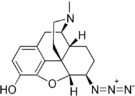

- Azidomorphine

Azidomorphine Azidomorphine |